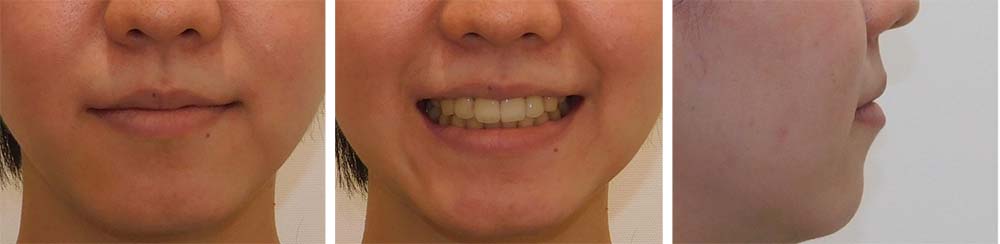

| 症例分類 | 叢生、上顎前突、口唇突出 |

| 診断名 | 下顎重度叢生を伴う骨格性上顎前突 |

| 主訴 | 歯並びが悪い、ものがよく噛めない、口元が気になる、歯科医師に勧められた |

| 年齢 | 22歳10ヶ月 |

| 性別 | 女性 |

| 抜歯部位 | 上下左右の第一小臼歯(4本) |

| 使用装置 | 表側のワイヤー装置 |

| 治療期間 | 2年2ヶ月 |

| 保定装置 | 固定式保定装置、取り外し式保定装置(8時間) |

下顎前歯重度叢生と上顎歯列の前方位、口唇閉鎖不全、口唇突出感があるため、上顎両側第一小臼歯と下顎両側第一小臼歯を抜去して治療を行いました。上顎前歯をしっかりと舌側移動しないといけなかったため矯正用アンカースクリューを使用しました。

前歯がしっかりと舌側移動できたため、口唇閉鎖不全が改善され口唇突出感もなくなり、問題なく咬合させることができました。